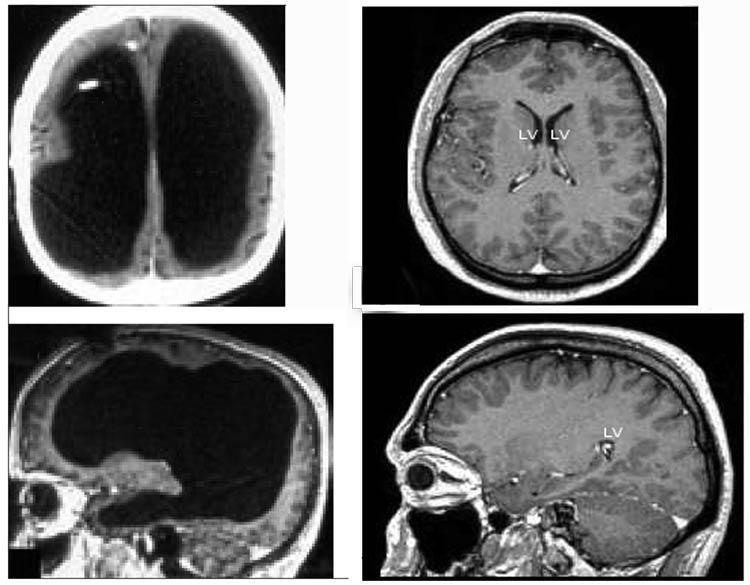

Команда ученых из США опытным путем выяснила, что удаление одного из полушарий головного мозга — далеко не конец всему. Дело в том, что если полушарие или его часть удалить, то происходят сложные изменения в оставшейся части мозга. Существующие функциональные связи упрочняются, образуются новые, происходит ряд процессов, который дает возможность человеку оставаться человеком и без части мозга.

Дальше других продвинулись ученые из команды Дорит Климан из Калифорнийского университета. Специалисты изучили истории болезни шести человек, которым в детстве удалили полушарие — полностью или частично. При этом общались эти люди нормально, проблем с речью или другими когнитивными способностями не было, не имели они и каких-либо физических недостатков.

Ученые предположили, что все это стало возможным благодаря тому, что пациенты пережили операцию в очень раннем возрасте — от нескольких месяцев от рождения до 11 лет. Самому младшему участнику обследования на момент осмотра было 20 лет, старшему — 31 год.

Добровольцев обследовали при помощи специального метода, который дает возможность проанализировать функциональные связи мозга без выполнения добровольцем какой-либо работы или без воздействия на человека. Ученые решили особенно тщательно изучить зрительную, соматомоторную кору головного мозга, дорсальный и вентральный зрительные пути, которые связаны с работой внимания и лимбическую систему. Плюс проанализировали лимбическую систему, когнитивные функции и так называемую сеть пассивного режима работы мозга.

Была у ученых и контрольная группа добровольцев, у которых никаких операций на мозге не проводилось. Как оказалось, у всех добровольцев из первой группы функциональные связи были значительно прочнее, чем у представителей контрольной группы.

Ученые считают, что за годы, которые прошли с момента операции, связи в мозге организовались так, чтобы заменить собой утраченные органы. Сеть пассивного режима, которая обычно занимает оба полушария, была очень хорошо сохранена в оставшемся полушарии у людей, чей мозг был поврежден.

Так что можно с уверенностью говорить о том, что мозг после повреждения восстанавливается. Причем восстановлению подлежат даже функции целого полушария, а не каких-то небольших органов. Как уже говорилось выше, когнитивные способности добровольцев были на нормальном уровне. О каких-либо проблемах, вроде низкого интеллекта, не сообщается. Интересным нюансом оказалось то, что лучше всего функции утраченного полушария восстановились как у человека, который лишился этой части мозга в три месяца от роду, так и у пациентки, которой провели аналогичную операцию в 7 лет.